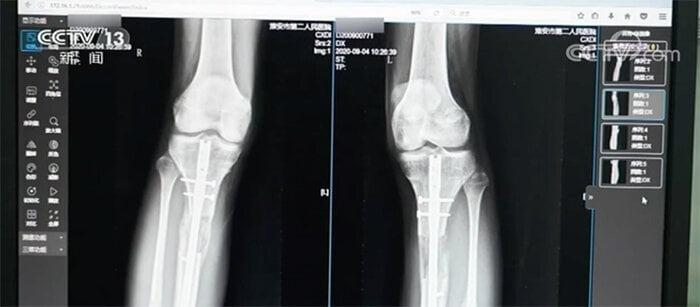

Ngoài Tiểu Hi và Tiểu An, có không ít người khác phải gánh chịu hậu quả nặng nề sau phẫu thuật tăng chiều cao. Năm 2020, Bệnh viện Nhân dân số 2, thành phố Hoài An, Giang Tô (Trung Quốc) tiếp nhận một bệnh nhân nam 22 tuổi.

Vì không hài lòng với chiều cao của mình, anh đã ra nước ngoài làm phẫu thuật kéo dài chân và sau đó là đôi chân bị nhiễm trùng nặng. Anh không thể đi lại, thậm chí còn phải đối mặt với nguy cơ tàn tật suốt đời.

Đôi chân của bệnh nhân nam 22 tuổi sau phẫu thuật kéo dài chân. (Ảnh: Jxnews)